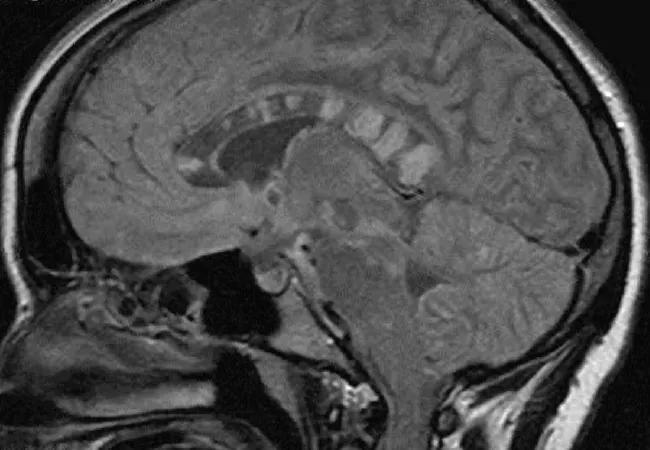

15-RHE-2815-Hajj-Ali-Inset-Figure-03

Figure 3. Sagittal T2-weighted FLAIR image (MRI) showing four particularly large “snowball” lesions in the posterior halfof the corpus callosum in a patient with Susac syndrome. Reprinted from Journal of the Neurological Sciences, vol. 299, Rennebohm et al., “Susac’s syndrome — update,” p. 87, © 2010, with permission from Elsevier.